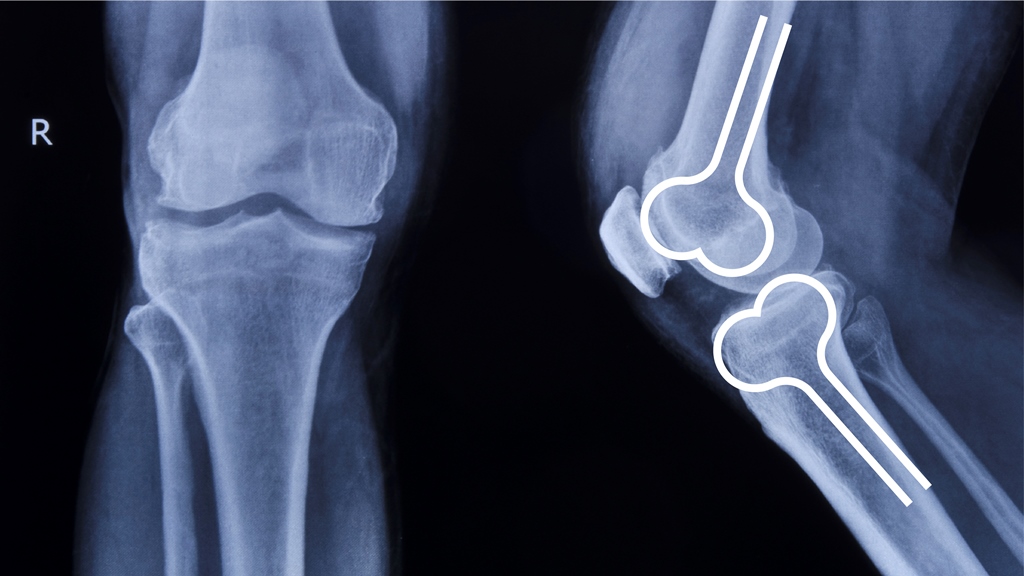

María del Pilar, es una Ortopedista muy especial, ya que su especialidad es la Ortopedia y traumatología en niños, una actividad que le permitió soñar con independizarse y crear su imagen, el desafío era construir su marca con los ingredientes que más la representan: energía, amor y cuidado con el que asume su formación. Este es el desarrollo de su marca.